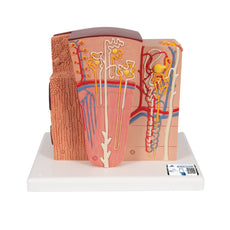

This Urinary System all-in-one-model shows:- Structures of retroperitoneal cavity

- Large and small pelvis with bones and muscles

- Inferior vena cava

- Aorta with its branches including iliacal vessels

- Upper urinary tract

- Rectum

- Kidney with adrenal gland.

One front half of a kidney is removable from the anatomical model of the urinary system. With easy to change male insert (bladder and prostate, front and rear half) and female insert (bladder, womb and ovaries, 2 lateral halves) the Urinary System model is a great teaching tool.